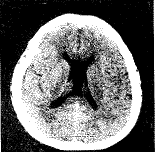

随着科学技术的发展,神经内窥镜手术的应用范围不断扩大。作为外科手术的一项新技术,神经内窥镜技术已应用到从诊断到治疗的神经外科许多领域。最近我院神经外科配置了美国Ckarus公司生产的神经内窥镜治疗系统,其中包括脑室镜、观察镜、治疗镜及与之配套的显微手术器械,我们应用该套设备行脑室-腹腔分流管的置入和脑脓肿的清除术数例,行第三脑室内蛛网膜囊肿合并脑积水和透明隔囊肿造瘘术各1例 ......